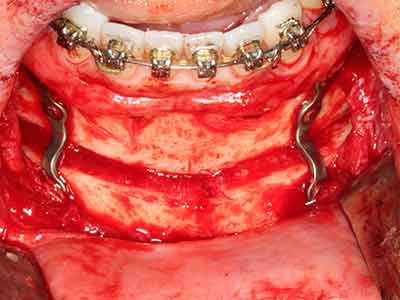

Bone tissue is not simply a mineral structure but also contains a substantial proportion of collagen fibres. This means it not only has good compressive strength but also a degree of flexibility, which can be taken advantage of when performing bone augmentations. In the classical expansion procedure using bone splitting, the atrophied alveolar ridge is split longitudinally and carefully expanded after reaching an adequate osteotomy depth (Fig. 13-16), ideally without substantial removal of the periosteum (Brugnami, Caiazzo et al. 2014, Stricker, Fleiner et al. 2014). Screw and plate systems with increasing expansion distance have proven effective in separating the two bone lamellae while remaining below the fracture threshold. In general, residual bone widths of at least 3–4 mm are required (Chiapasco, Zaniboni et al. 2006) to guarantee adequate flexibility and sufficient bone coverage of the future implants. If necessary, a vertical relief osteotomy on one or both sides can improve flexibility. A combination with additional augmentation techniques, particularly on the buccal side, has been described as an alternative to the classical technique.

The splitting procedure is particularly atraumatic and there is no significant loss of dimension when using piezosaws, and there are no significant differences between implants in split jaws and implants in an alveolar ridge without a bone deficit (Chiapasco, Zaniboni et al. 2006, Danza, Guidi et al. 2009). However, sufficient continuous irrigation is essential, particularly with locally restricted and deep splitting to prevent thermal stress in the apical osteotomy regions.

Fig. 13: Adequate irrigation with the 4-mm residual bone width is essential for this 52-year-old patient during the bone splitting.

Fig. 14: Placement of four tapered RSX implants (Bego Implant Systems, Bremen).

Fig. 15: The one-year follow-up x-ray examination shows stable conditions at the bone level.

Fig. 16: The intraoral conditions are also stable with embedding of the implants in keratinized gingiva.